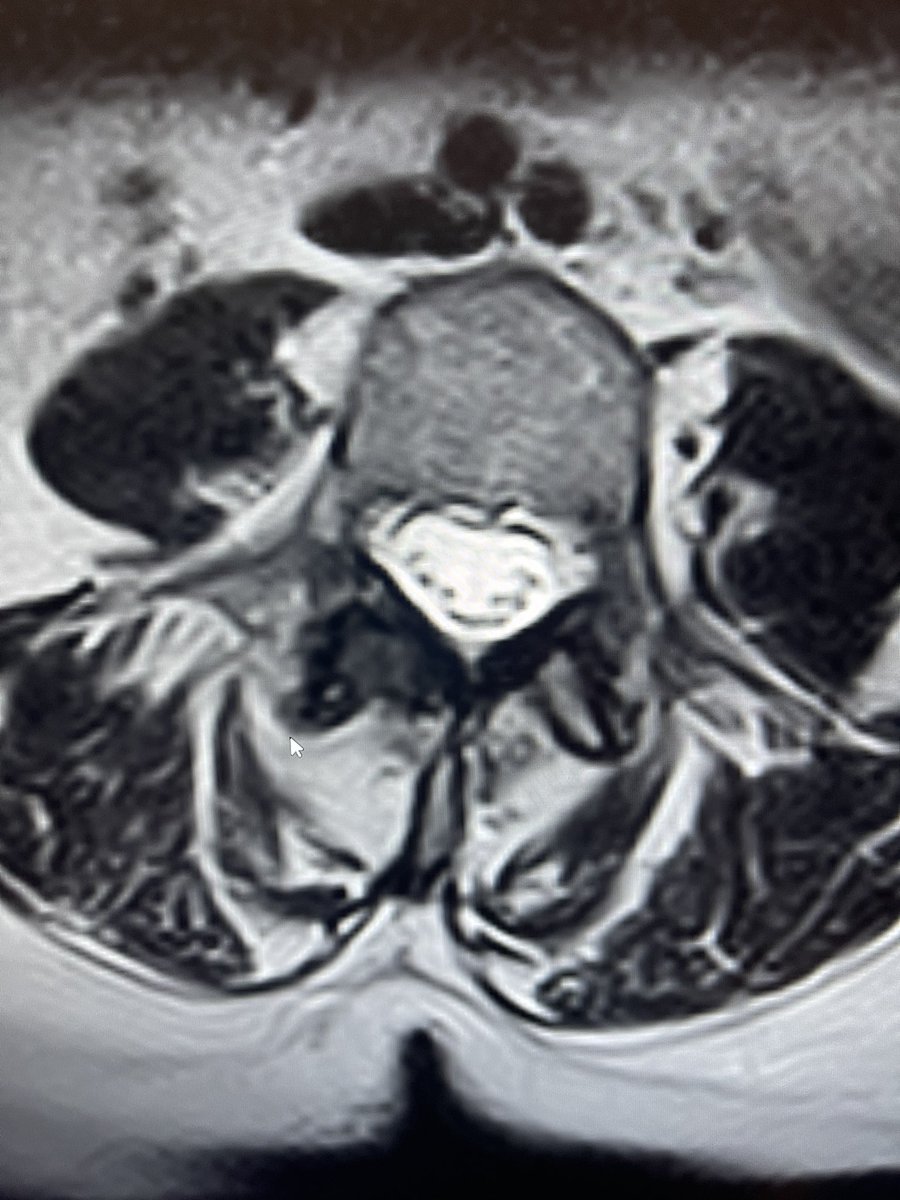

So, this is some real talk regarding #MSKIR in the real world.

@TheStrykerIVS makes a great product, #SpineJack, that shows up in a lot of cool posts on this and other platforms.

This example was just posted by @neuroradiology - a great example of the genre.